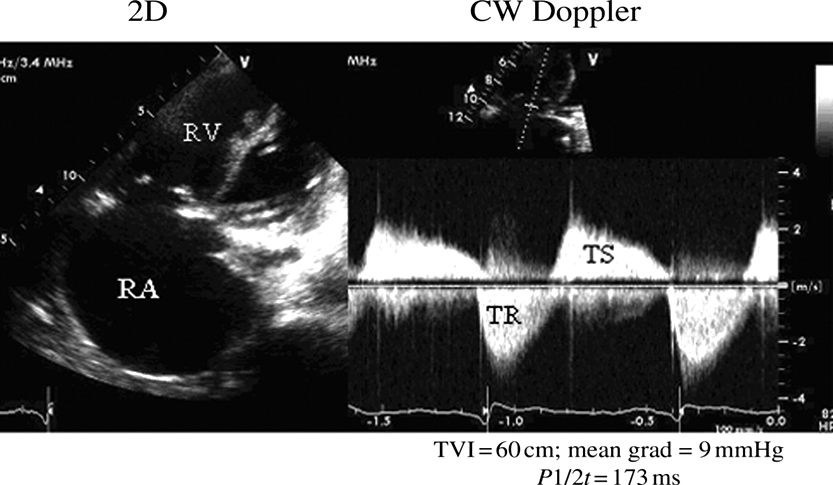

TV stenosis (CW)

DECREASED E-F SLOPE

OBTAIN TVA USING

PHT METHOD

NORMAL TVA 7-9 CM

TRACE E & A WAVE TO OBTAIN MEAN PG

Severity Scale